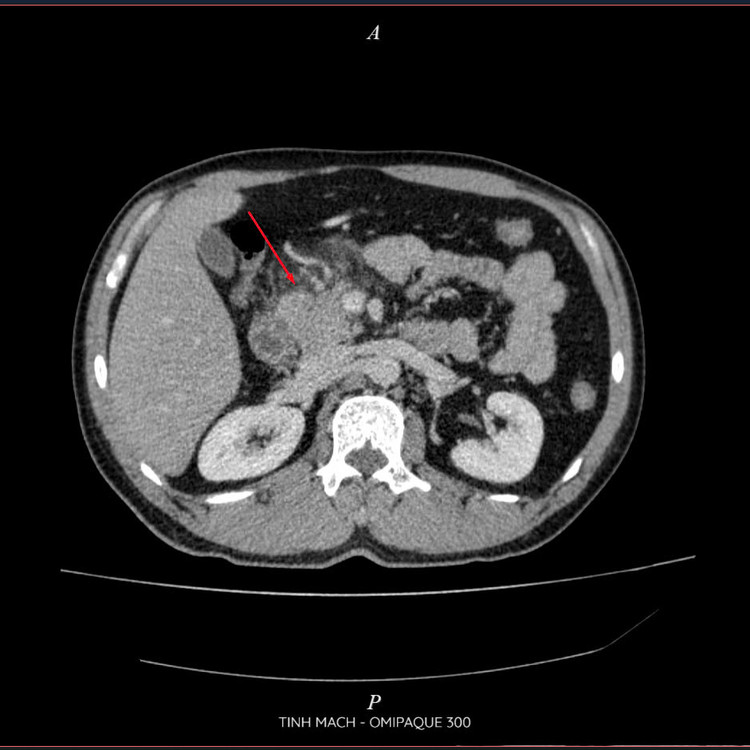

| Viêm tụy cấp trên phim chụp - Ảnh BVCC |

Kết quả chụp CT Scanner đa dãy ổ bụng có thuốc cho thấy: Hình ảnh viêm tụy cấp Balthazar D, mCTSI 4 điểm, xét nghiệm máu triglycerid >73 mmol/ l, khí máu có tình trạng toan Lactat>2. Nhận thấy đây là tình trạng viêm tụy cấp nặng do tăng triglyceride, các bác sĩ khoa Hồi sức cấp cứu Bệnh viện Đa khoa Hùng Vương đã tiến hành lọc máu hấp phụ cho bệnh nhân với mục tiêu là giảm triglycerid, và giảm phản ứng viêm.